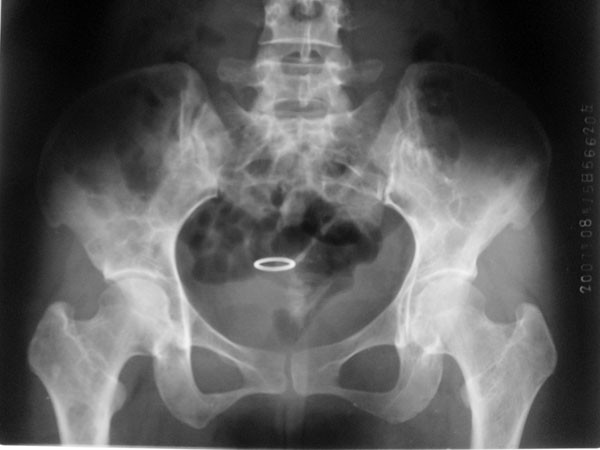

标题: CT10087:女,29岁,多发肿瘤样病变。

车祸致t12压缩性骨折,行ct扫描意外发现椎体多发肿瘤样病变,建议加拍骨盆平片,患者平常无症状。

2/t12压缩性骨折。脾挫裂伤(建议继续扫描或b超检查)

1:胸腰椎多发破坏伴骨折,近似穿凿样,考虑骨髓瘤,但有好多不符只出1、发病年龄小、女性,2、病变似有硬化环。2:淋巴瘤可能性大,骨及脾脏均有改变(脾脏改变似与外伤关系不大)建议密切结合临床及相关检验进一步诊断,期待结果。